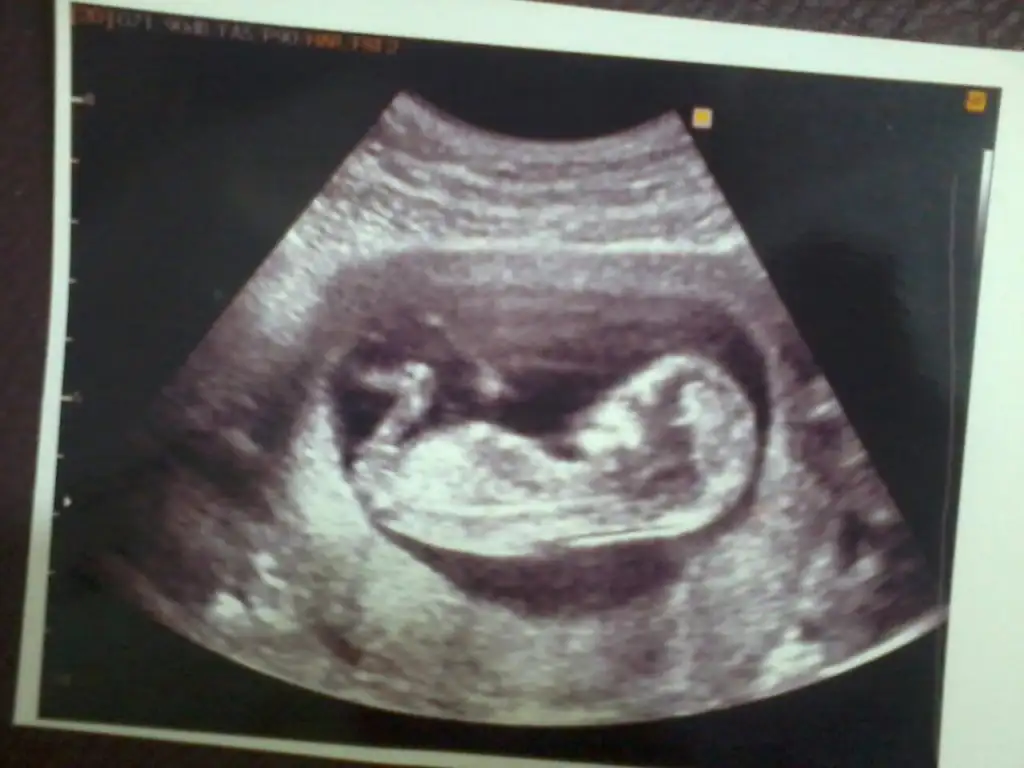

Kesin kizz diyorum...Merhaba arkadaşlar bu foto arkadaşımın bebeği yorum yaparsanız çok sevinirim burada 13 haftalık

Eki Görüntüle 1469137